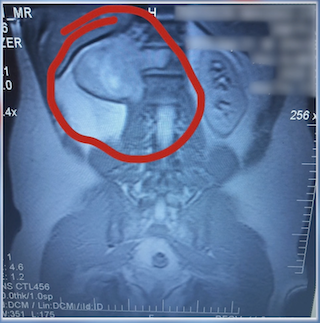

• Magnetic resonance imaging (MRI) scan uses radio waves and a powerful magnet to produce detailed images of bones to check for problems.